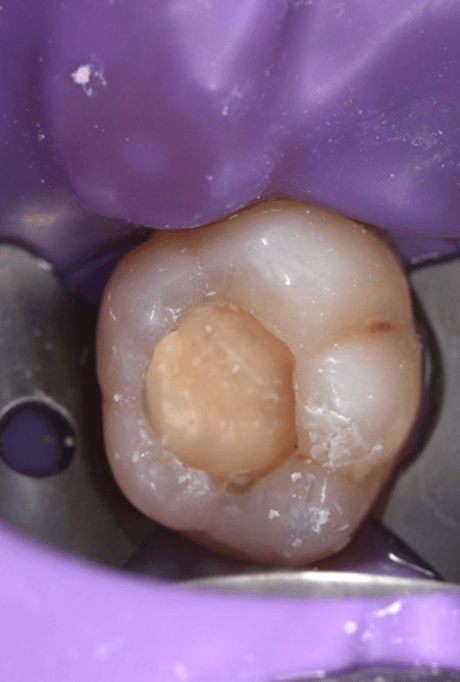

Before Photo

Dr Deesha